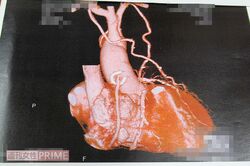

「救急車が家に到着するまで20分、車内で15分かけて心電図を取り、病院に引き受けてもらう交渉に10分かかり、ようやく出発しました。私は胸の痛みに耐えるため、必死にこぶしを握り締めていて、内出血ができるほどでした。そして診断結果は、急性心筋梗塞。運よく搬送先の病院には心臓血管の専門医がいて、すぐにバイパス手術を受けて助かりました」

「でも、中身の心臓はボロボロで、いつ発作が起こるかわからない状態の“内部障害者”なんです」